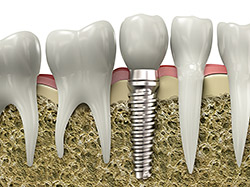

Implant Restoration

If you have missing teeth, it is crucial to replace them. Without all your teeth, chewing and eating can destabilize your bite and cause you discomfort. When teeth are missing, your mouth can shift and even cause your face to look older. Implants are a great way to replace your missing teeth, and if properly maintained, can last a lifetime!

An implant is a new tooth made of metal and porcelain that looks just like your natural tooth. It’s composed of two main parts: One part is the titanium implant body that takes the place of the missing root, and the second part is the tooth-colored crown that is cemented on top of the implant. With implant treatment, you can smile confidently knowing no one will ever suspect you have a replacement tooth.

In addition to tooth replacement, implants may be used to anchor dentures, especially lower dentures that tend to shift when you talk or chew. For patients with removable partial dentures, implants can replace missing teeth so you have a more natural-looking smile.